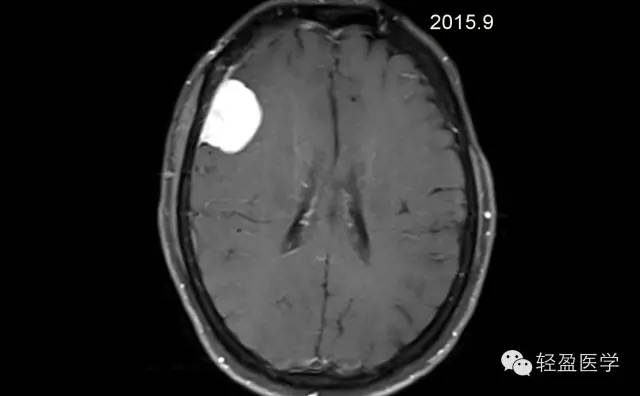

【病例】颅内肿瘤,脑内?脑外?

病理为:小细胞恶性肿瘤,考虑为(外周)原始神经外胚层肿瘤,(复发)。以下是病例结果及分析。